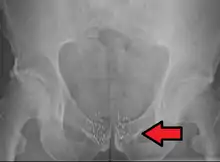

Применяется в лечении онкологических заболеваний по методу брахитерапии. Множество миниатюрных герметичных капсул с 125I хирургически помещают в область опухоли, где они убивают пораженные клетки ионизирующим излучением распада иода-125.[7][8]